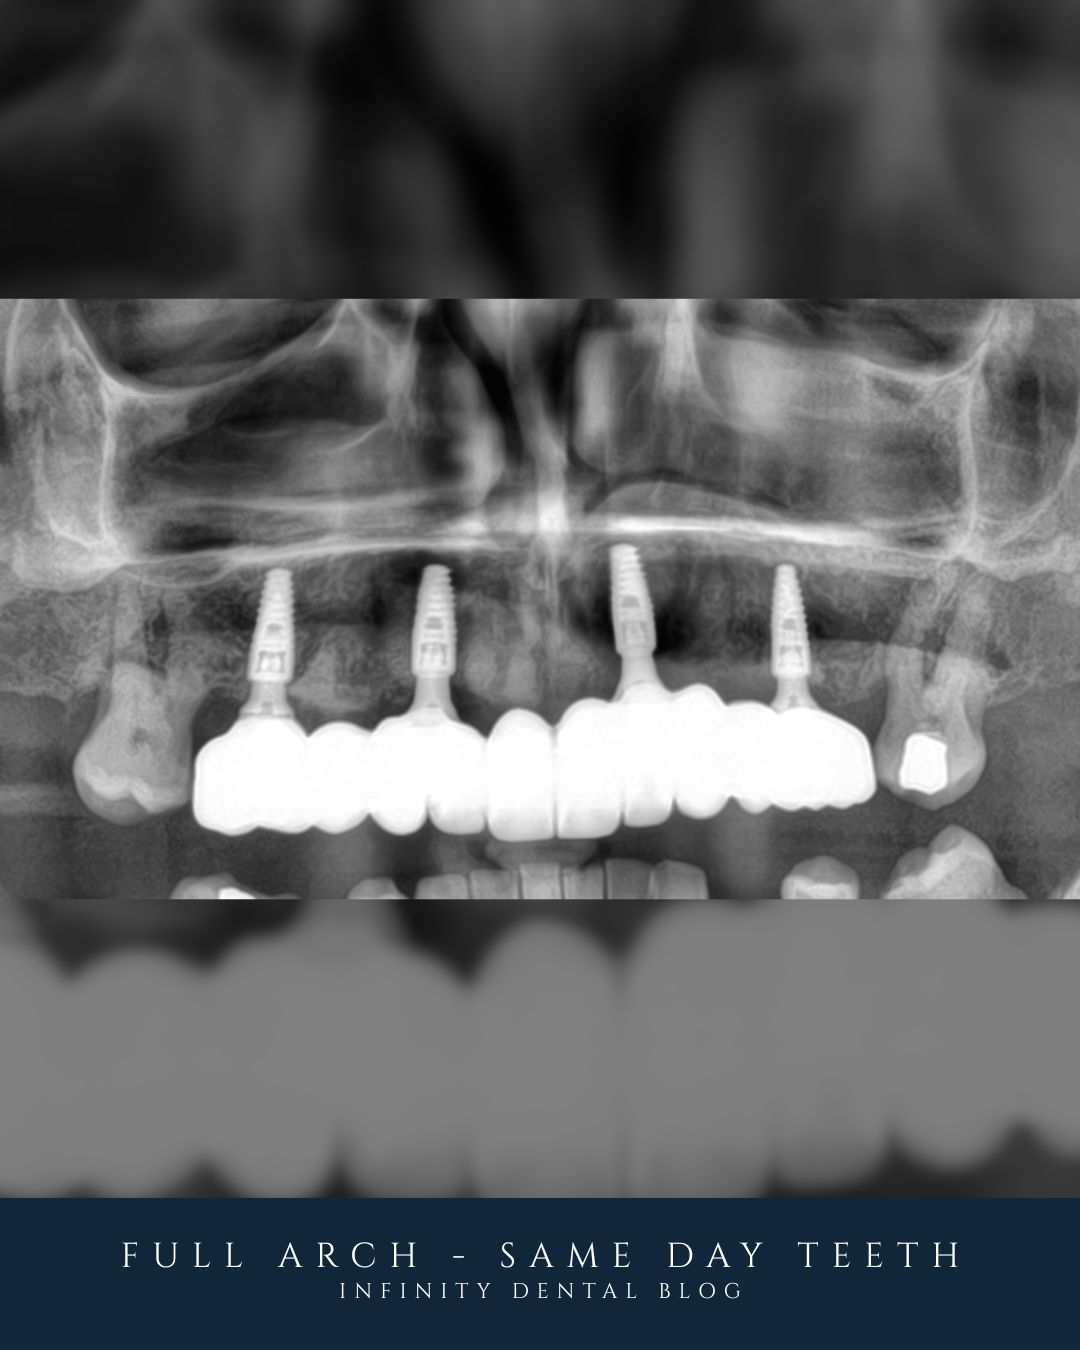

We carried out same day teeth with implants on the upper arch. That means the failing teeth are removed, implants are placed, and a fixed set of teeth is fitted all in one morning. In this case it was carried out under IV sedation, making the appointment feel like it passes far quicker and is much more relaxed. It avoids months of waiting without teeth and gives immediate function and confidence. For the lower teeth, the plan is to look after what she still has and keep them going for as long as possible with focused periodontal care.